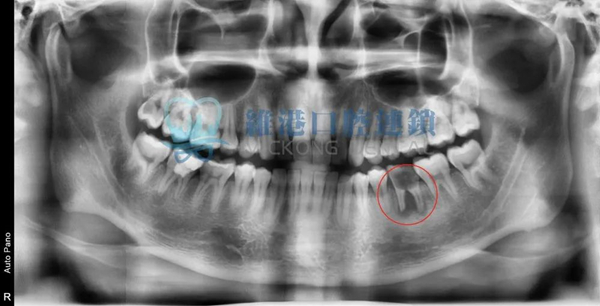

輕微案例